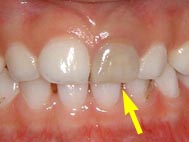

歯ぐきがめくれた

ぶつけ方によって付着歯肉(骨の上にある歯ぐきで、堅い部分)がめくれるように傷つくことがあります。左の写真は矢印の間で裂けてしまい、付着歯肉がめくれている状況です。歯は打っておらず、動揺などはありませんでした。この様な場合は剥がれた歯ぐきを元の位置に戻し、縫合する必要があります。放っておくと付着歯肉が下がった状態で治癒してしまい、傷あとを残す場合があります。右の写真は受傷から2ヶ月後の写真です。傷あともなく完全に治癒しています。